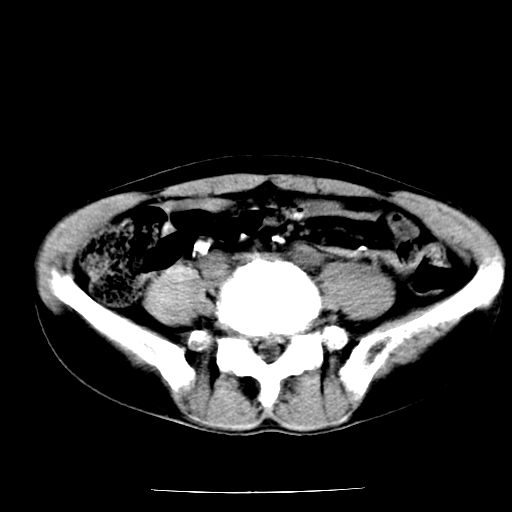

两肺结核并右侧胸腔积液;脾脏、腹腔及腹膜后淋巴结结核[陈旧性];肝内胆管结石

胸部腹部都是结核(双肺。纵隔淋巴结,肝脏,脾脏,肠系膜)

两肺结核并右侧胸腔积液;脾脏、腹腔及腹膜后淋巴结结核[陈旧性];肝内胆管结石。直肠息肉?